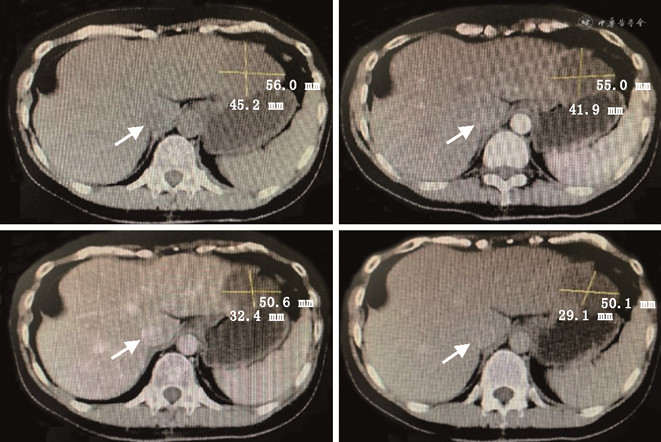

患者女,1963年3月出生,既往体健,曾接种过乙肝疫苗,2011年10月31日因“体检发现肝脏占位10余天”入院。入院时患者无任何不适症状,既往无手术史,无长期药物使用史,无烟酒嗜好,无放射性物质、化学物品等接触史。入院查体:神志清,精神可,营养状态良好,皮肤巩膜未见黄染,无出血点,无肝掌、蜘蛛痣;心肺听诊无殊;全身浅表淋巴结未触及,全腹平软,无压痛、反跳痛,未触及腹部包块,肝脾肋下未及;肝区叩击痛(-),Murphy征(-),移动性浊音(-),肠鸣音4次/min。实验室检查:肝功能正常,乙肝系列检查HBsAb92.83↑、HBcAb0.008↓,其余指标正常;肿瘤标记物CEA、AFP、CAl99、CAl25等均在正常范围内。影像学检查:肝脏B超(本院2011-10-20)显示:右肝及大小约3.0 cm×3.0 cm×3.6 cm实质偏低回声结节区,边界可及;胆脏B超:大小形态正常,壁上及约0.6 cm偏强回声结节,向囊内隆起,胆总管未见明显扩张。提示:右肝实质低回声团块,建议进一步检查;胆囊息肉。全腹部CT平扫+增强(本院2011.10.21)显示:肝脏各叶大小比例正常,肝右叶前上段见一团状低密度影,大小约26 mm×24 mm,边缘略模糊;增强后病灶边缘略强化,延迟后病灶有缩小,肝内外胆管不扩张。上腹部MR平扫+增强(本院2011-10-25)显示:肝脏各叶大小比例正常,肝右叶前上段见一团块异常信号灶,大小约29 mm×31 mm,T1低信号,T2高信号,DWI稍高信号;增强早期病灶边缘强化,延迟后病灶有明显缩小,肝内外胆管不扩张。提示:肝右叶前上段占位,不典型的血管瘤可能,胆管细胞癌不能完全排除,请结合临床建议进一步检查。排除手术禁忌后于2011年11月2日在全身麻醉下行右肝部分切除术,术中见肿块位于右肝第Ⅶ段,大小2.0 cm×3.0 cm、色灰白、质地硬,累及肝脏表面,决定行右肝部分切除术。术后常规病理(本院2011-11-09)示:(右肝)上皮样血管内皮瘤(低-中度恶性)(图1)。免疫组化:本院:Vim(+++)、CD34(+++)、CD31(++);HMB-45、S-100、CK7、CK19、CK8/18均(-);浙江大学医学院第一附属医院:CK(+/-)、CK19(-)、Hep(-)、Ki-67(5%+)、CD34、CD31、Fli-1均(+++)。

患者第1次出院后未进行药物治疗,定期在我院或浙江大学医学院第一附属医院复查肝胆B超和(或)上腹部CT,均未发现明显异常。上腹部CT平扫+增强(2018-04-19)影像所见:肝右叶部分切除术后,肝左叶低密度结节影,范围约34 mm×52 mm,边界清;平扫CT值约32 HU,延迟期边缘呈结节样轻度强化,病灶有缩小(图2)。影像诊断及建议:肝右叶部分切除术后;肝左叶占位,血管内皮瘤可能性大,其他病变不除外,请结合临床必要时进一步检查。患者于2018年5月9日第2次入院,实验室检查示:肝功能正常,乙肝系列检查HBsAb48.180↑、HBcAb0.010↓,其余指标正常;肿瘤标记物中CA724 13.94↑,其余肿瘤标记物CEA、AFP、CAl99、CAl25等均在正常范围内。排除手术禁忌后于2018年5月12日行腹腔镜下左肝部分切除术,术中用超声刀游离左肝叶周围组织,用腹腔镜下直线切割闭合器分离离断左肝外叶。术后病理(本院2018-05-16)示:(左肝)上皮样血管内皮瘤(直径6.5 cm)(图3)。免疫组化B片:AFP(-)、CD31(+++)、CD34(+++)、CD19(-)、CK7(-)、CK8/18(-)、D2-40(灶+)、Vim(++)。免疫组化诊断结果:B片:AFP(-)、CD31(+++)、CD34(+++)、CD19(-)、CK7(-)、CK8/18(-)、D2-40(灶+)、Vim(++)。

患者第2次手术后同样未进行药物治疗,仅进行定期复查。全腹部CT平扫+增强(本院2020-11-06)示:尾状叶类圆21 mm×23 mm稍低密度伴轻度强化,肝裂旁稍肿大淋巴结(图4);肝右叶部分切除术后,肝左叶占位术后,请结合临床。肝尾状叶占位灶,转移瘤待排,建议进一步检查。实验室检查(本院2020-11-05)示:肝功能正常,乙肝系列检查HBsAb86.800↑、HBcAb0.010↓,其余指标正常;肿瘤标记物CEA、AFP、CAl99、CAl25、CAl53、CA724等在正常范围内。排除禁忌后于2020年11月7日行复杂肝癌切除术,术中充分暴露肝尾状叶,用超声刀、氩气刀切除肝尾状叶并予以残端止血。切除的尾状叶送病理科行术中冰冻快切病理检查,诊断为(肝脏)上皮样血管内皮瘤。病理组织学诊断结果(本院2020-11-13):(1)(肝脏)上皮样血管内皮瘤(肿块大小2.5 cm×2.0 cm;图5),伴见脉管内瘤栓,切缘阴性,送检(第7、8、9、1、3、12组)3/13个淋巴结见肿瘤细胞转移;(2)部分肝组织;(3)注:该肿瘤组织免疫组化提示CK8/18及AFP阳性,提示该肿瘤存在向上皮成分分化。免疫组化诊断结果:E片:CD31(+++)、CD34(+++)、FLI-1(+++)、CK8/18(+++)、CK19(-)。H片:AFP(+)、CD31(+++)、CD34(+++)、CK19(-)、FLI-1(++)、CK8/18(+)、D2-40(-)、Ki-67(+)15%、Vim(+++)、EMA(-)。